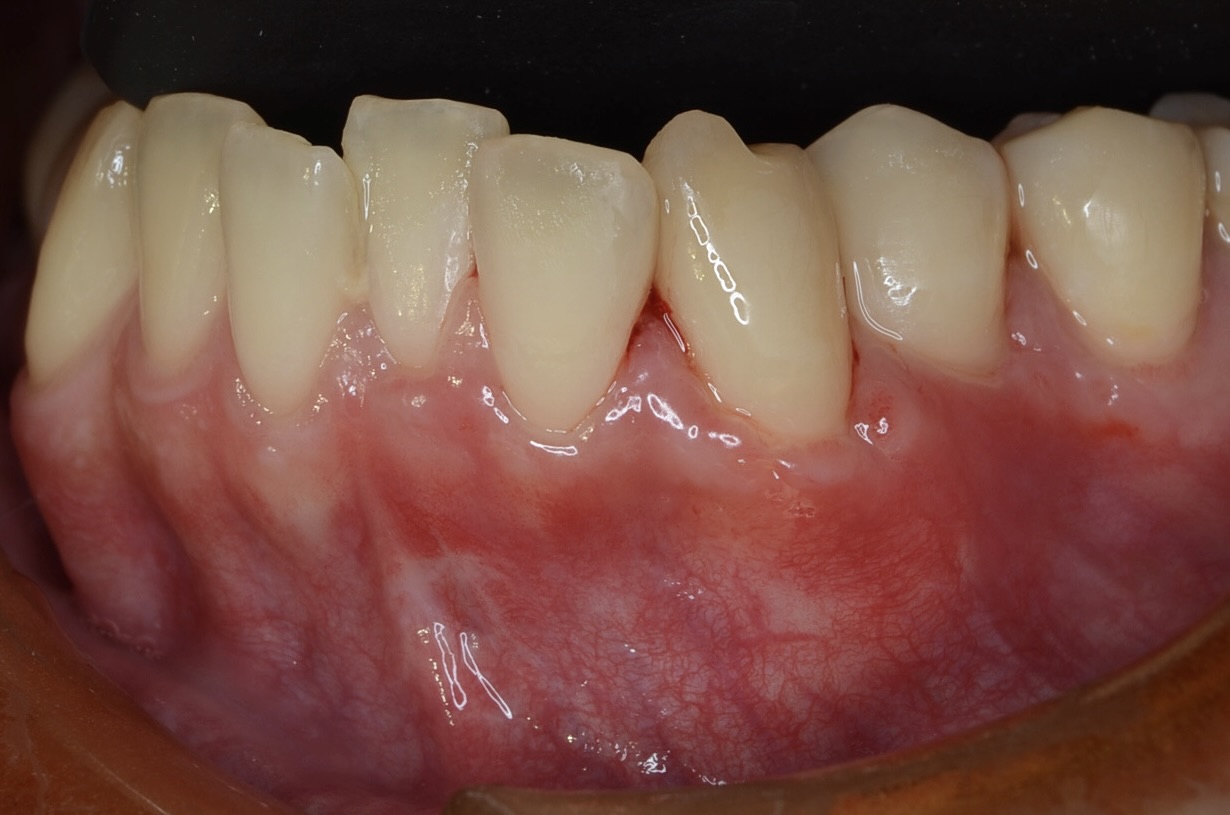

術後4週間

根面被覆が達成されています。